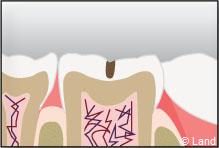

Un inlay reconstitue l’anatomie dentaire en comblant une cavité taillée dans la dent.

L’inlay-onlay reconstituera la dent comme la dernière pièce d’un puzzle. Il sera véritablement collé dans la dent.

Il aura un rendu naturel et présentera une meilleure étanchéité assurée par le collage, il sera aussi plus durable que d’autres types de reconstitutions dites foulées.

Exemple d’un onlay molaire